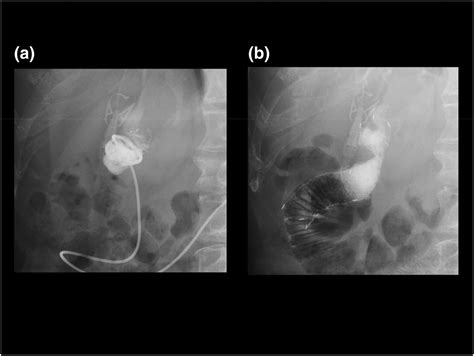

Diagnostic Approaches

Diagnosing this condition requires a combination of clinical suspicion and advanced imaging techniques. Because the symptoms can mimic other gastrointestinal issues, such as gallbladder disease or pancreatitis, accurate diagnostics are essential. Medical professionals typically employ the following methods:

Computed Tomography (CT) Scan Visualizes the distended afferent limb and identifies the site of the obstruction.